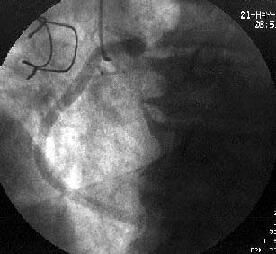

徢椺丗61嵨丄抝惈丅

婛墲楌丗58嵨帪偵DeBakey II宆偺媫惈戝摦柆夝棧偵偰Bentall弍(Piehler朄)傪巤

峴丅59嵨帪偵偼暊晹偵媫惈戝摦柆夝棧傪敪徢偟丄堦帪峈嬅屌椕朄傪拞抐偟偨偑偦

偺屻嵞奐丅

尰昦楌丗暯惉14擭5寧屵慜0帪傛傝摢栩晹捝偑弌尰偟丄嫻晹傊捝傒偑曻嶶偡傞傛偆

偵側傝7帪偵摉堾傪媬媫庴恌偝傟傑偟偨丅

棃堾帪尰徢丗寣埑86/66mmHg丆柆攺106/min丒惍丅岥怬偵僠傾僲乕僛傪擣傔偨丅怱

揹恾偱QRS暆偺奼戝偲I, aVL, V4-6偵ST忋徃傪擣傔丄媫惈怱嬝峓嵡偵傛傞怱尨惈

僔儑僢僋偲恌抐偟丄嬞媫僇僥乕僥儖専嵏傪巤峴偟傑偟偨丅

怱憻僇僥乕僥儖専嵏丗RCA偵嫹嶓昦曄傪擣傔傑偣傫偱偟偨偑丄LCx傊collateral傪

擣傔傑偟偨乮Figure1乯丅堷偒懕偄偰LCA偺憿塭傪帋傒傑偟偨偑丄JL僇僥乕僥儖偑

偳偆偟偰傕engage偱偒傑偣傫偱偟偨丅戝摦柆憿塭傪巤峴偟丄塃姤愲偺塃懁忋曽偵

憿塭嵻偺pooling傪擣傔傑偟偨乮Figure2乯丅擖岥晹偱姰慡暵嵡偟偰偄傞偲峫偊摨

晹埵偵懳偡傞僀儞僞乕儀儞僔儑儞傪巤峴偡傞偙偲偲偟傑偟偨丅擖岥晹偑塃懁忋曽

偵懚嵼偡傞偨傔丄僈僀僨傿儞僌僇僥乕僥儖偼丄JR僇僥乕僥儖傪巊梡偟傑偟偨

乮Figure3乯丅

側偍丄恖岺寣娗偺擖岥晹偺摨掕偵旕忢偵擄廰偟丄専嵏奐巒屻偡偱偵栺30暘偑宱夁

偟偰偄傑偟偨丅屇媧忬懺偑偝傜偵埆壔偟偮偯偗偨偨傔丄恖岺屇媧娗棟偲偟傑偟

偨丅寣埑傕掅壓偟偰偄傑偟偨偑丄DOA5兞掱搙偱80-90戜傪堐帩偟偰偄傞忬嫷偱偟

偨丅IABP偺憰拝傕峫偊傑偟偨偑丄戝摦柆夝棧偑懚嵼偟偰偄傞偨傔巊梡偟傑偣傫偱

偟偨丅

姤摦柆僀儞僞乕儀儞僔儑儞丗僈僀僨傿儞僌僇僥乕僥儖偺engage偑埆偄偨傔丄儔僕

僆僼僅乕僇僗丒儚僀儎乕偱僇僥乕僥儖傪屌掕偝偣側偑傜彊乆偵儚僀儎乕傪恑傔偰

偄偔偲丄彮偟偯偮寣娗偑憿塭偝傟傞傛偆偵側傝丄恖岺寣娗偲LMT偺暙崌晹偵崅搙

嫹嶓傪擣傔傑偟偨乮Figure4乯丅傑偨丄嵍姤摦柆撪偵嫄戝側寣愷傪擣傔傑偟偨丅

摉帪寣愷媧堷偺僨僶僀僗偑側偔丄媧堷偼偱偒傑偣傫偱偟偨丅暙崌晹偵懳偟偰丄

MAVERICK4.0mm偱POBA傪峴偄丄偦偺屻LAD偵嫄戝側寣愷偑棳傟偰偄偔偺偑妋擣偝傟

傑偟偨乮Figure5乯丅NIR4mm僗僥儞僩傪棷抲偟暙崌晹嫹嶓偼夵慞偟傑偟偨偑丄LAD

偺no flow傪擣傔傑偟偨丅nicorandil偍傛傃UK傪姤拲偟偨偲偙傠丄flow偑夵慞偟

偨偨傔庤媄傪廔椆偟傑偟偨乮Figure6乯丅